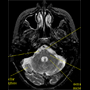

MRI of

horizontal section in

human